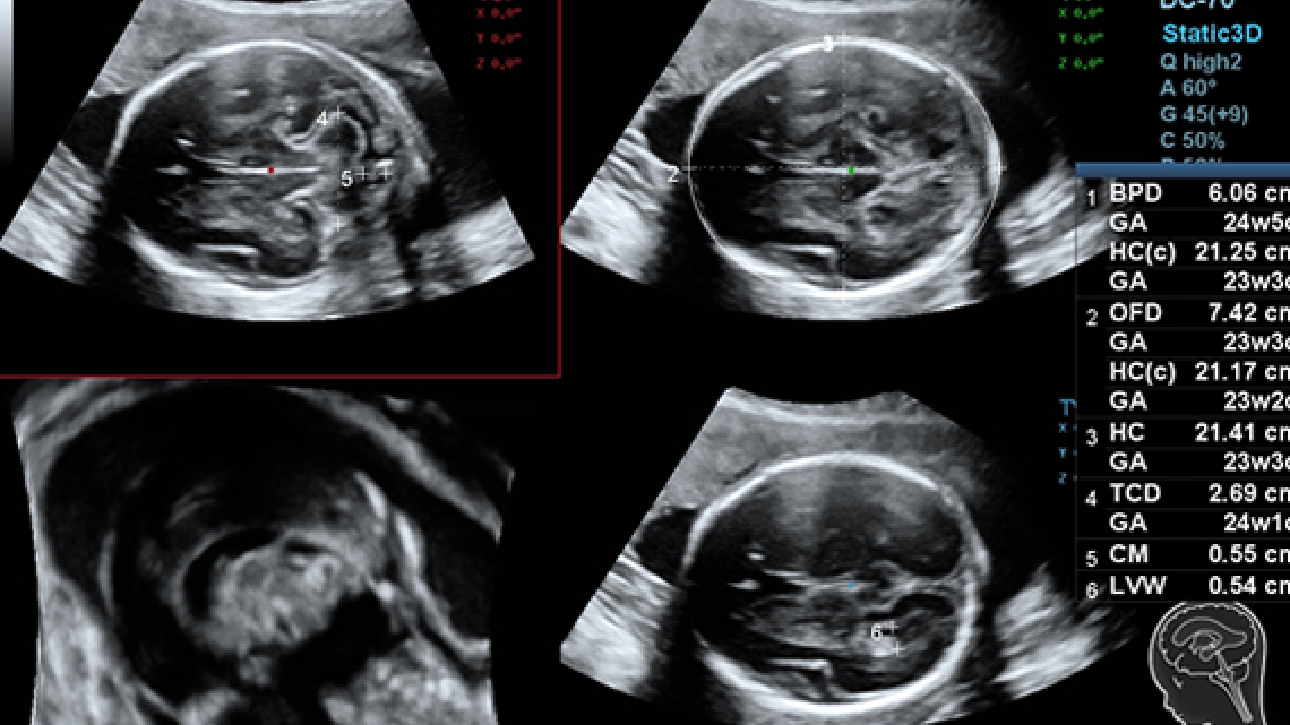

DC-70 Exp

–°–Њ–≤–Љ–µ—Б—В–љ–Њ —Б —Б–Њ–≤—А–µ–Љ–µ–љ–љ—Л–Љ–Є —Г–ї—М—В—А–∞–Ј–≤—Г–Ї–Њ–≤—Л–Љ–Є —В–µ—Е–љ–Њ–ї–Њ–≥–Є—П–Љ–Є –љ–Њ–≤–Њ–µ —А–µ—И–µ–љ–Є–µ –Њ—В Mindray –њ—А–µ–Њ–±—А–∞–Ј—Г–µ—В –∞–Ї—В—Г–∞–ї—М–љ—Л–µ –Ј–∞–і–∞—З–Є –Ї–ї–Є–µ–љ—В–Њ–≤ –≤ –Ї–ї–Є–љ–Є—З–µ—Б–Ї–Є–µ –њ–Њ—В—А–µ–±–љ–Њ—Б—В–Є.

–°–Є—Б—В–µ–Љ–∞ DC-70 Exp —Б X-Insight –њ–Њ–Љ–Њ–≥–∞–µ—В —Г–њ—А–∞–≤–ї—П—В—М –њ–Њ–≤—Б–µ–і–љ–µ–≤–љ–Њ–є –Ї–ї–Є–љ–Є—З–µ—Б–Ї–Њ–є –њ—А–∞–Ї—В–Є–Ї–Њ–є —Б –ї–µ–≥–Ї–Њ—Б—В—М—О –Є —Г–≤–µ—А–µ–љ–љ–Њ—Б—В—М—О.

–Ю—Б–љ–Њ–≤—Л–≤–∞—П—Б—М –љ–∞ –≥–ї—Г–±–Њ–Ї–Њ–Љ –њ–Њ–љ–Є–Љ–∞–љ–Є–Є –њ–Њ—В—А–µ–±–љ–Њ—Б—В–µ–є –Ї–ї–Є–µ–љ—В–Њ–≤, –Ї–Њ–Љ–њ–∞–љ–Є—П Mindray —А–∞–Ј—А–∞–±–Њ—В–∞–ї–∞ —Б–Є—Б—В–µ–Љ—Г DC-70 Exp —Б X-Insight, —З—В–Њ–±—Л –Њ–±–µ—Б–њ–µ—З–Є—В—М eXpress Clarity, eXceptional Intelligence, eXceeding Experience.